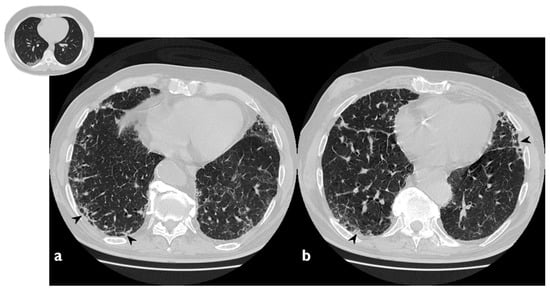

3.4. Nodular Pattern

A complete resolution after therapy was observed in three of the five cases with nodular pattern (Figure 11), whereas two subjects have shown a partial reduction in number and size. Only one patient did not report nodule resolution after treatment. In one patient—who did not show nodules or masses at the first CT—we have observed the presence of new nodular lesions despite therapy (Figure 12) (Table 7).

Figure 11. On the left (a): baseline HRCT; peripheral solid nodule in the right lower lobe (arrowheads). On the right (b): HRCT after oral corticosteroid (OCS) therapy; the previous nodule is no longer present.

Figure 12. On the left (a): baseline HRCT. On the right (b): follow-up HRCT; a new nodule (arrowhead) appeared in the left lower lobe.